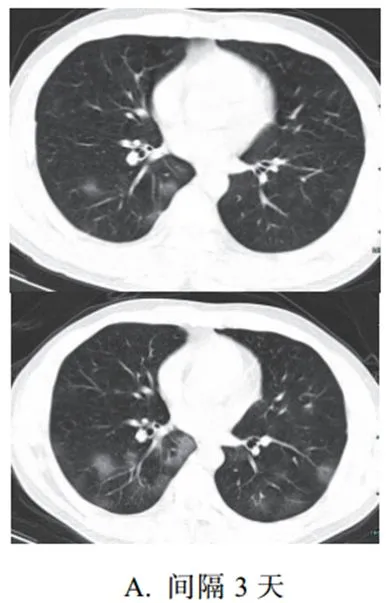

新冠肺炎大多数病例进展迅速,复查 CT 影像发生明显变化

表现为病灶数目明显增多,范围明显扩大,密度增高,病灶分布由外周向中央推进

根据既往 SARS 病理学机制,提示为肺泡腔内聚集大量细胞渗出液、间质内血管扩张渗出;肺泡连通起来形成融合态势(图 2-11)

图 2-11 病灶数目增多、范围扩大 (A-D)